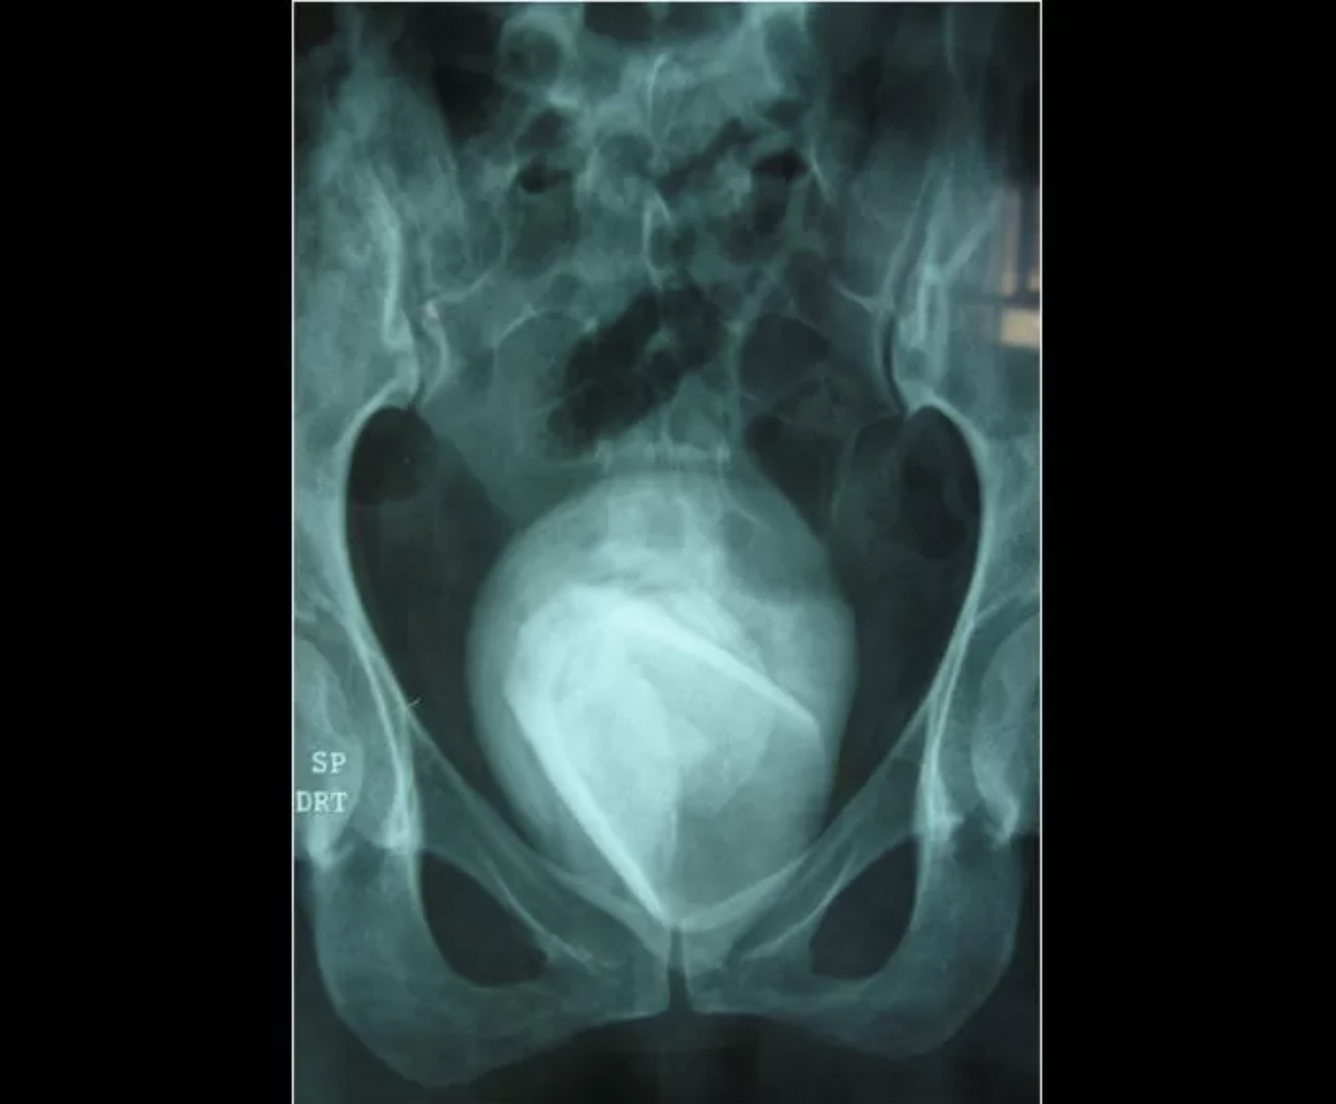

결국 대학 병원을 찾았고 의사들은 원인은 알아보기 위해서 엑스레이 촬영을 했다.

결과는 매우 충격적이었다.

그녀의 몸 안에 가로, 세로 각각 8cm 크기의 거대한 방광 결석이 들어있었기 때문.

심지어 그 결석을 갈라보니 유리컵으로 보이는 이물질이 있었다.